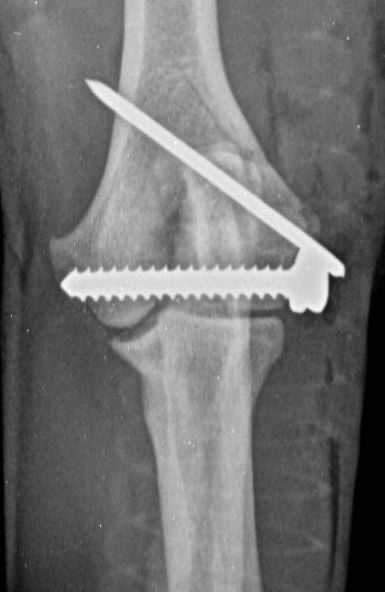

These concerns have led to recommendations being altered over the past decade or so, with veterinarians now using bone plates, instead of K-wires, as an adjunct to a transcondylar screw when managing humeral unicondylar fractures (Figure 2), even in puppies (Figure 3) (Clark, 2016; Kvale et al., 2022). However, the basis on which this conclusion for puppies was reached appears to have been flawed because it assumed that what had been shown to be the case for adults would also apply to immature patients. As the conclusion was felt to conflict with the author’s experience of treating such patients, a retrospective study was undertaken to evaluate complications and outcomes in immature dogs treated for humeral unicondylar fractures at one centre over a 10-year period (Butterworth, 2022). The findings of this study are summarised in this article.

Therefore, if the current trend towards the use of epicondylar plates, rather than K-wires/pins, in combination with a transcondylar bone screw to manage humeral unicondylar fractures in adults is also adopted for skeletally immature patients, we might well be throwing the puppy out with the bath water. The exception might be when the epicondylar ridge shows comminution, which means that a single K-wire might not provide enough stability, or when the patient shows prodromal lameness (both of which were noted in the patient related to Figure 3).